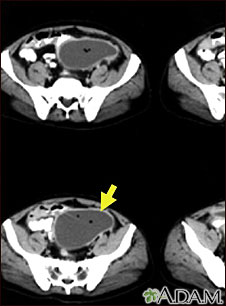

- CT scan

Tests to locate the abscess include:

Often, a sample of fluid will be taken from the abscess and tested to see what type of germ is causing the problem.